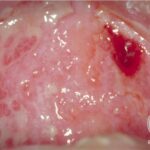

See the illustration below depicting ocular cicatricial pemphigold disease

- Mouth involvement presents as recurrent, painful erosions. The gingivae are most commonly involved, followed by the palate and the buccal mucosa; however, any mucosal site in the mouth may blister. Involvement of the oropharynx may present with hoarseness or dysphagia. Progressive scarring disease may lead to esophageal stenosis requiring dilatation procedures. Supraglottic involvement may lead to airway compromise requiring tracheostomy.

- Oral erosions often begin on the gingiva, particularly near the teeth. Erosions can also be seen on the palate, the buccal mucosa, the lips, the posterior part of the pharynx, the tongue, and the floor of the mouth. Intact blisters are rarely seen, but they may appear flaccid or tense.